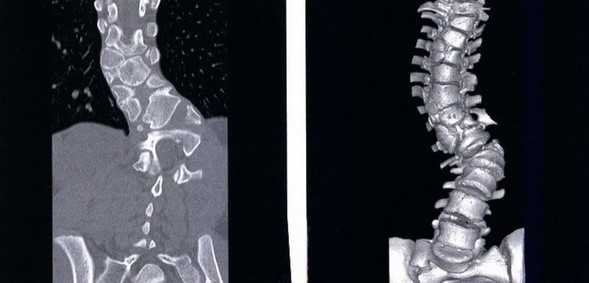

Сколиоз позвоночника на снимках КТ